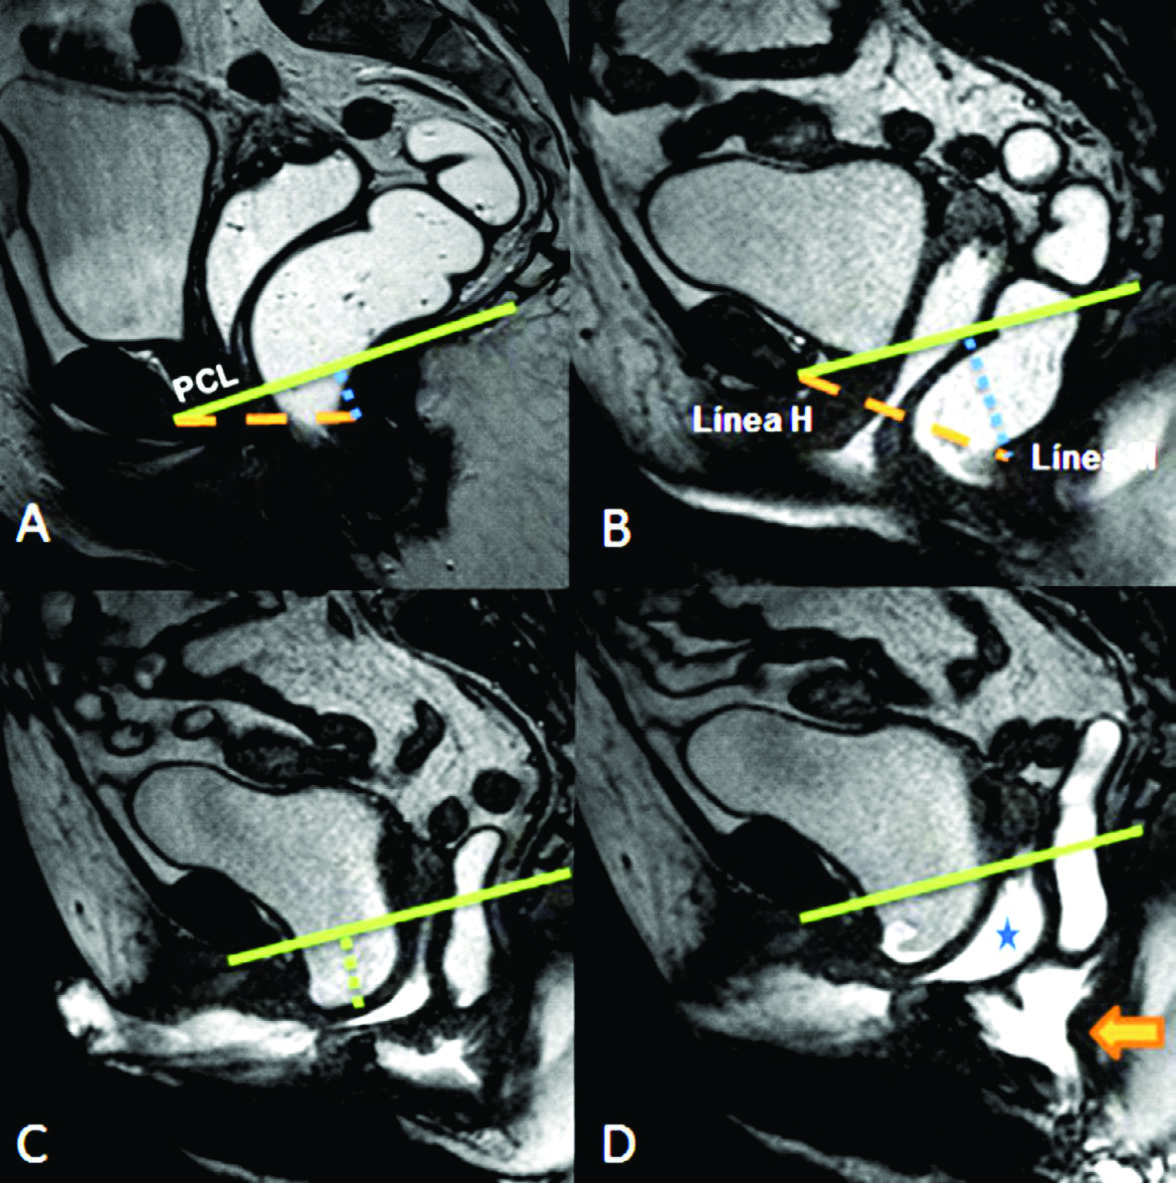

Figura 10

Rectocele eversión

A) Imágenes potenciadas en T2 de alta resolución en el plano sagital a nivel de la línea media de una mujer durante el reposo.

B) TRUE FISP sagital durante maniobra de Valsalva.

C-D) TRUE FISP sagital durante defecación. Se evidencia cistocele, prolapso vaginal y eversión del recto. Las líneas punteadas azules cuantifican la severidad de los prolapsos.

La línea H se traza desde el borde inferior del pubis hasta la pared posterior del recto a la altura de la unión ano rectal, representando el diámetro anteroposterior del hiato urogenital, con un valor normal menor a 6 cm (Ver figuras 4).

La línea M es perpendicular a la PCL a nivel del sector más posterior de la línea H y representa el descenso del hiato del elevador, con un valor normal menor a 2 cm. El ángulo ano rectal es el ángulo entre el eje central del canal anal y la pared posterior del recto, con un valor normal entre 108º y 127º y una variación de hasta 15º en Valsalva.

Además se debe valorar la relajación del piso pélvico, a través del valor que adquiere tanto la línea H (apertura del hiato urogenital) como la línea M (descenso del piso pélvico) durante las maniobras dinámicas (Ver tabla 4) (7).